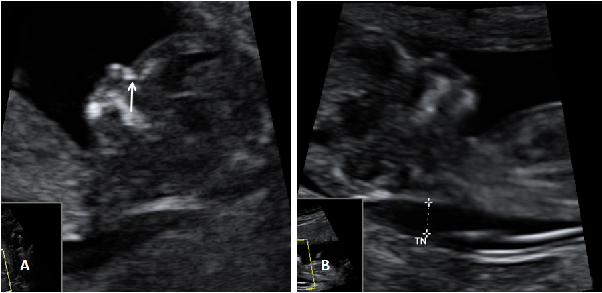

La insuficiencia tricúspide del feto se diagnostica con ecografía Doppler en la semana 12 de gestación. Es un marcador ecográfico de anomalías cromosómicas. Estudia el flujo de sangre que pasa a través de la válvula que une la aurícula derecha con el ventrículo derecho. Cuando da unos valores alterados se recomiendan otras pruebas más invasivas para verificar que el bebé no sufre síndrome de Down.